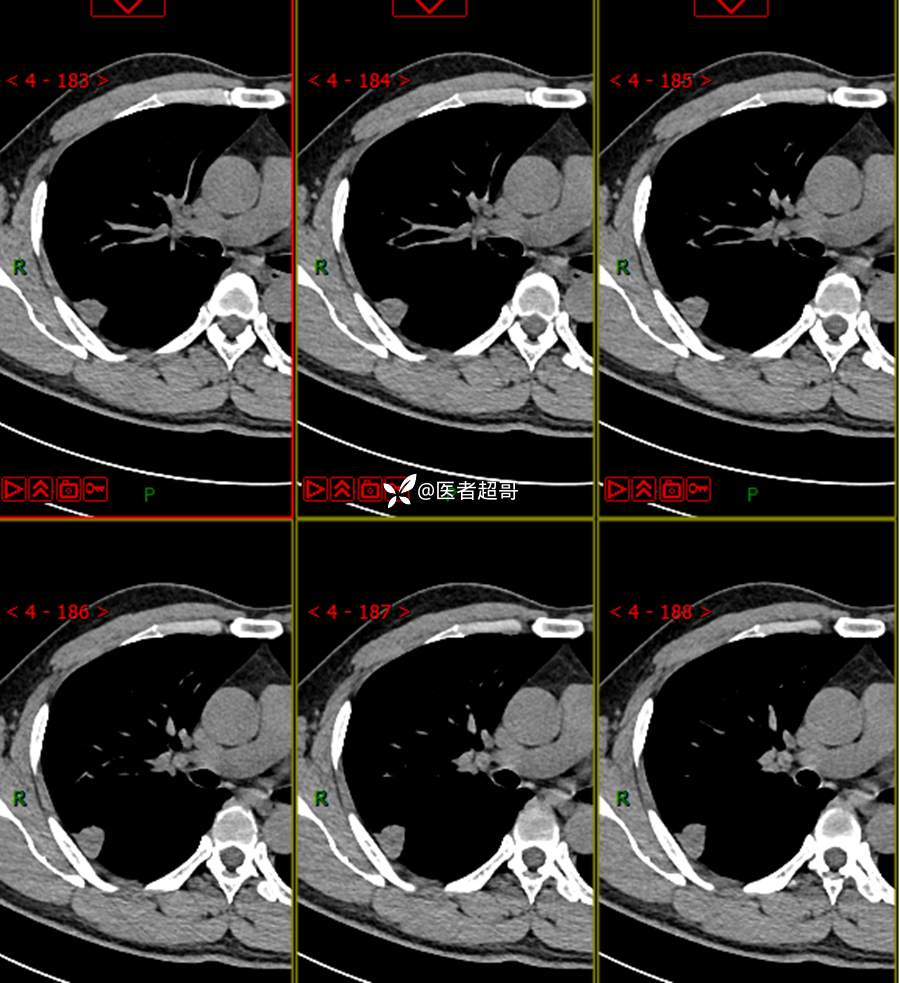

现病史:患者1年余前于体健中心行胸部X片发现右上肺叶密度增高影,无明显咳嗽,咳痰,无痰中带血及咯血,无胸痛及胸闷、气短,无发热、盗汗及全身乏力。无头痛、头晕,无腹痛、腹胀及恶心、呕吐,无声音嘶哑及呛咳,未行特殊治疗。后患者定期复查胸部CT,未见明显变化。2023-2-6患者于我院复查胸部CT:右肺上叶、下叶交接处胸膜下见实性结节影,最大截面约2.6cm×1.4cm,较前增大,建议行手术治疗。今为求进一步诊治,遂来我院就诊,门诊以“肺肿物”收入我院,患者自发病以来,神志清,精神可,饮食可,睡眠良好,大小便正常,近期体重未见明显增减。